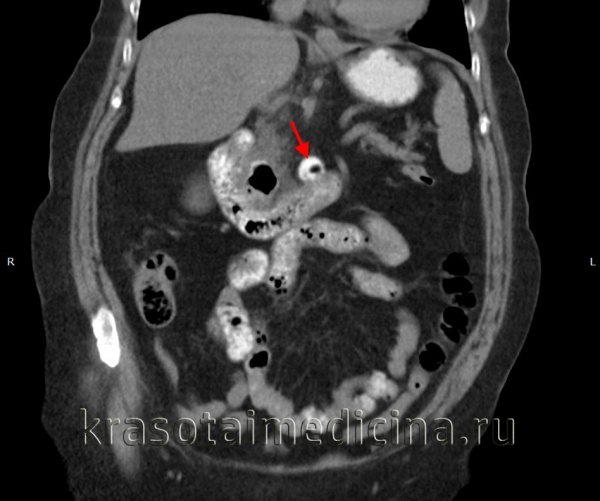

КТ ОБП. Дивертикул горизонтальной части 12-перстной кишки, заполненный частично контрастом, частично – газом.

Мультиспиральная компьютерная томография:

Наиболее безопасным методом диагностики дивертикулярной болезни, как в период скрытого течения, так и при диагностике осложнения является компьютерная томография, позволяющая не только подтвердить наличие у пациента дивертикулов, но и определить характер осложнений. К ним относятся острый дивертикулит с перфорацией, абсцессом, перитонитом.